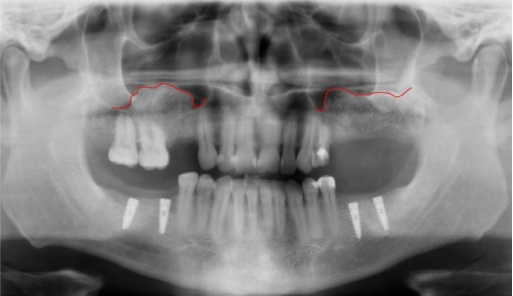

Before